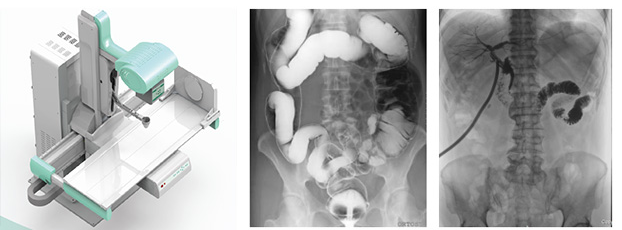

3、要擁有適宜床體高度的動態檢查床及全面的床體運動功能,以輕松實現各種普通及特殊造影檢查,如食道造影、消化道造影、結腸雙對比造影、T管造影、靜脈腎盂造影(IVP)等。同時動態dr要支持醫生回放造影視頻,并可以抽幀,輔助疾病診斷。

4、多功能動態dr還標配全身拼接功能,可以為骨科關節置換、脊柱矯形等手術提供全下肢或全脊柱拼接影像。